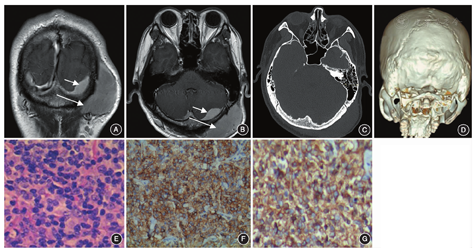

患者男,32岁,因发现左枕部肿块且进行性增大1年余入院。患者1年余前无意中发现左侧枕部头皮肿块,于外院行手术切除,术后病理学结果示淋巴组织增生。术后4个月病变复发并逐渐增大而来我院就诊。体格检查:左枕部头皮可触及一约7.5 cm×8.0 cm×2.0 cm大小的质韧肿块,边界清晰,无压痛及波动感,活动度差,头皮外观正常。左侧颈部可触及数个肿大淋巴结,余全身浅表淋巴结未扪及肿大。神经系统未见阳性体征。患者既往无外伤史、免疫抑制剂治疗史以及获得性免疫缺陷综合征(acquired immunodeficiency syndrome, AIDS)病史。血常规未见异常,头颅MRI示左枕部头皮下、颅板下脑外占位性病变,累及枕部硬膜和左侧横窦,左侧枕叶和左侧小脑半球轻度受压(图1A,图1B)。头颅CT示左侧顶枕部头皮下软组织密度肿块影,大小约7.5 cm×7.7 cm×2.4 cm,邻近颅骨骨质未见吸收破坏(图1C)。颈部淋巴结超声检查提示,双侧颈部、左侧锁骨上窝可见多个淋巴结,部分淋巴结可见肿大。胸腹CT示右肺内侧段少许条索影,前上纵膈内密度略增高,腹腔脏器未见确切病灶。患者拒行开颅手术,仅行头皮下肿块切除。术中见肿块组织呈淡黄色,位于枕部肌肉层,血供丰富,与周围组织分界尚清。将皮下肿块全部切除,切除范围至正常肌肉。肿块基底部侵袭枕骨骨膜,将受累骨膜一并切除,对应部位枕骨外观正常,未见虫蚀样改变,术毕留取标本送检。术后病理结果提示滤泡性淋巴瘤向弥漫性大B细胞淋巴瘤转化可能性大(图1E)。免疫组化结果显示:Bcl-2(+)、CD10(+)、MUM-1(+/-)、Bcl-6(+)、CD23(+)、CD35(+)、CD3反应性(+)、CD45RO反应性(+)、CD20(+)、CD79a(+)、cyclin D1(-)、CD5(-)、Ki-67:80%(+)。患者拒绝进一步治疗,自行出院后失访。